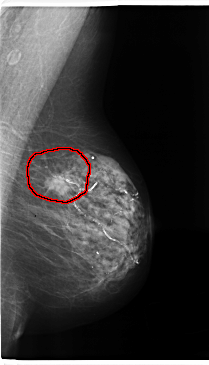

C_0196_1.LEFT_CC

FILE: C_0196_1.LEFT_CC.OVERLAY

TOTAL_ABNORMALITIES 1

ABNORMALITY 1

LESION_TYPE MASS SHAPE OVAL MARGINS SPICULATED

ASSESSMENT 5

SUBTLETY 5

PATHOLOGY MALIGNANT

TOTAL_OUTLINES 1

BOUNDARY